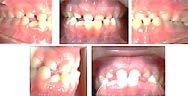

Se describe un caso clínico de un paciente de 14 años y 8 meses, diagnosticado con clase II esquelética, hiperdivergente, clase II molar dere cha, clase I molar izquierda, la relación canina no determinable, el overbite disminuido, el overjet aumentado, con apiñamiento moderado. Con los dientes 12 y 22 palatinizados, el 13 ectópico, con mordida abierta anterior, las líneas medias desviadas, con habito de empuje lingual. Obje tivos: mejorar el perfil facial, corrección del api ñamiento maxilar y mandibular, incorporar al arco los dientes 12,13, 22 y 23, mantener clase I molar izquierda, obtener clase I molar derecha, y canina bilateral, corrección de overjet y over bite, de las líneas medias dentales. Mejorar las relaciones esqueléticas, lograr correcta intercus pidación, la guía de desoclusión canina, la guía incisiva. Mejorar la salud periodontal. La apa ratología utilizada una rejilla lingual de Justus, brackets prescripción Roth 0.022x0.028, tubos bondeables 6´s y 7´s superiores e inferiores. Adicionalmente se realizó ameloplastía en los incisivos anteriores, extracciones de los prime ros premolares superiores, segundos premolares inferiores, terceros molares superiores e inferio res. La retención se llevó a cabo por medio de retenedores circunferencial superior con perla de Tucat y termoformado inferior. El tiempo de tratamiento fue de 2 años y 2 meses.

Reporte del caso

Paciente de 14 años y 8 meses, moti vo de consulta: “mi mordida no me gusta” el patrón esquelético es cla se II, hiperdivergente, clase II molar derecha y clase I molar izquierda, los caninos superiores en infraoclusión overbite disminuido, apiñamiento severo superior, moderado inferior, con los dientes 12 y 22 palatinizados, el 13 ectópico, con mordida abierta anterior, y las líneas medias desvia das.

Estudios de inicio extraorales

En las fotografías en la Figura 1 se observa el ligero dextrognatismo inferior, la línea facial se encuen tra desviada con respecto a la línea media dental superior e incompe tencia labial. El perfil es convexo, el tercio facial inferior se encuentra aumentada (Figura 2).

Estudios de inicio fotografías intrao rales en la de frente se ven la línea media dental superior esta desviada

hacia la derecha y la línea media dental inferior a la izquierda, con mordida abierta anterior, el canino superior derecho se encuentra fuera del arco ( Figura 3 ), en la oclusal superior los inci sivos laterales palatini zados y paladar ojival profundo, en la lateral derecha una relación molar clase II y relación canina no determinable (Figura 4), en la izquier da una relación molar clase I y relación canina no deter minada.

Resultados

En los estudios finales se observa en las fotografías extraorales: de sonrisa, (Figura 8) que persiste ligera asime tría facial, la línea facial coincidente con la línea media dental superior y

cierre total de la mordida con el perfil convexo, los tercios faciales propor cionados, mejoría de los tejidos blan dos y armonía facial.

En las fotografías intraorales fina les se muestra una relación molar y canina clase l, bilateral (Figura 9) las líneas medias coincidentes, la máxi ma intercuspidacion, la corrección del apiñamiento maxilar y mandibu lar, se mejoró el estado periodontal, una correcta intercuspidacion, guía incisiva y desoclusion canina.

En la radiografía lateral de cráneo (Figura 10) se ve una disminución del ángulo ANB a 5° y la retroclina ción de los incisivos superiores e infe riores.